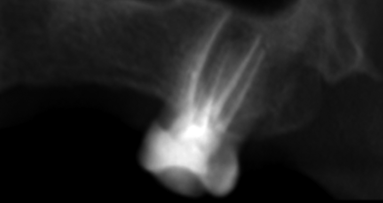

Case 4

This type of anatomy is the most challenging, as it requires all your skills and high-tech equipment. The patient was referred for irreversible pulpitis of a maxillary second molar. Upon examining the preoperative radiograph (Fig. 12), we could see that the anatomy was not clear. When creating the access cavity (Fig. 13), I saw only a small opening in the centre of the buccal area of the access cavity. Using ultrasonic instruments, very carefully and gently, I extended the access cavity more to the distal side and a bit deeper, preceding very slowly. It was like creating a second access cavity inside the first one. I had to go down almost 5 mm in order to uncover the opening of the distal canal, and the mesial canal and the isthmus between the two canals can be observed in Figure 14.

The immediate postoperative radiograph (Fig. 15) shows how deep the furcation and the isthmus between the two canals were. This kind of anatomy is very difficult to establish and treat in teeth to which access is relatively easy. We could unfortunately not find a micro-CT reconstruction of such an anatomy, as performing a root canal therapy on a maxillary second molar is not common, being rather difficult. We can easily miss a canal and thereby the whole treatment is jeopardised.

It is necessary to use the proper tools, such as a good dental microscope with good-quality lenses, good-quality front surface mirrors and high definition, ultrasonic instruments that will allow you to microsurgically create good access, and a suitable file system and chemical preparation to complete the treatment.